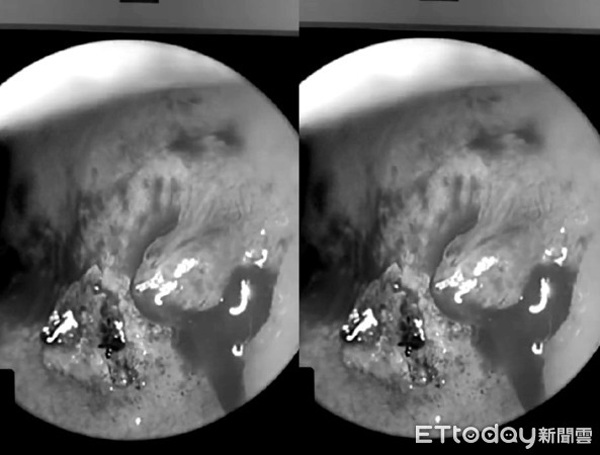

Một người đàn ông 24 tuổi ở Đài Trung, Đài Loan được bạn gái đưa tới viện cấp cứu vào đêm khuya, anh ta kêu bị chảy máu cam liên tục, dù đã dùng giấy chặn lại nhưng vẫn không ngừng chảy. Qua nội soi, bác sĩ nhận thấy mạch máu bị đứt cần vào phòng mổ phẫu thuật laser để cầm máu.